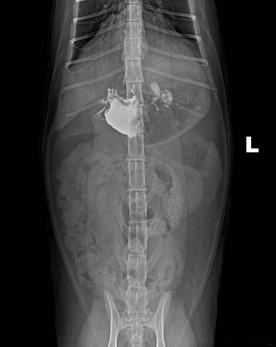

c.X线检查。对于阻线性较强的物质(如金属、骨头)较容易辨别,对于阻线性与组织密度相似的物体较难确定,但是可以通过消化道灌服造影剂判断是否有阻塞或可包裹物体。

机械性肠梗阻的读片要点:1.体积增大;2.形态轮廓变化;3.影像密度变化;4.浆膜细节变化。

犬猫呕吐的鉴别诊断,犬猫呕吐的诊断和治疗

金毛 线性异物